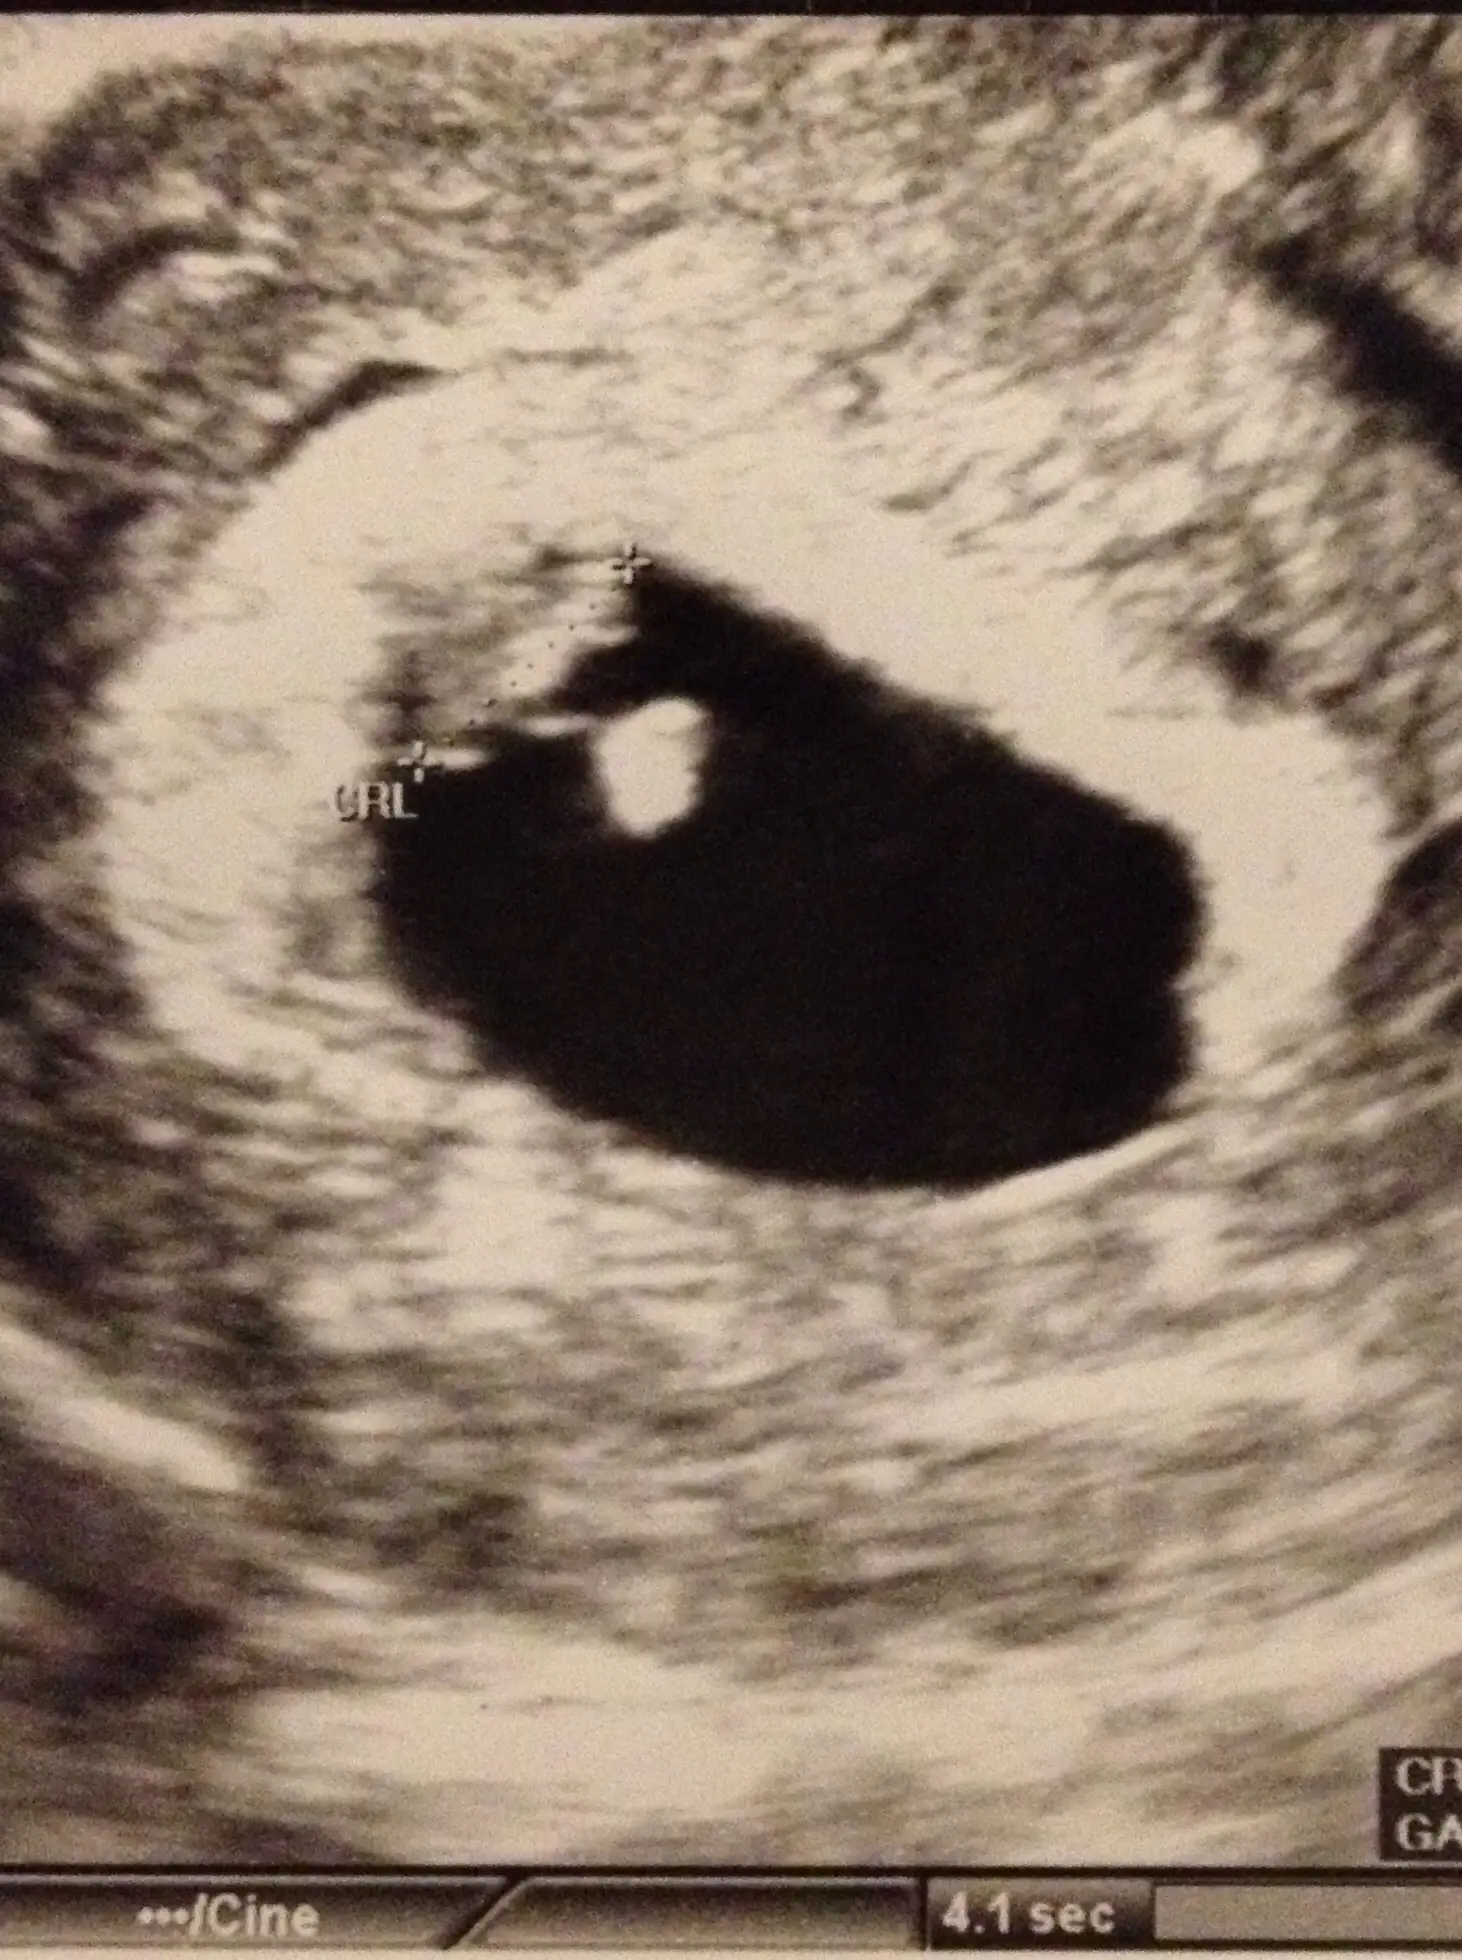

Kizlar gunaydin.biz de dun doktorumuza gittik.dogum tarimiz biraz ileri alindi bebek buyuklugunden dolayi.su an 6w5d olarak devam ediyoruz.